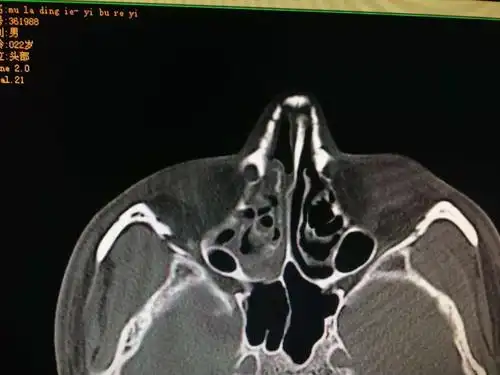

一例严重的鼻骨粉碎性骨折手术复位分享